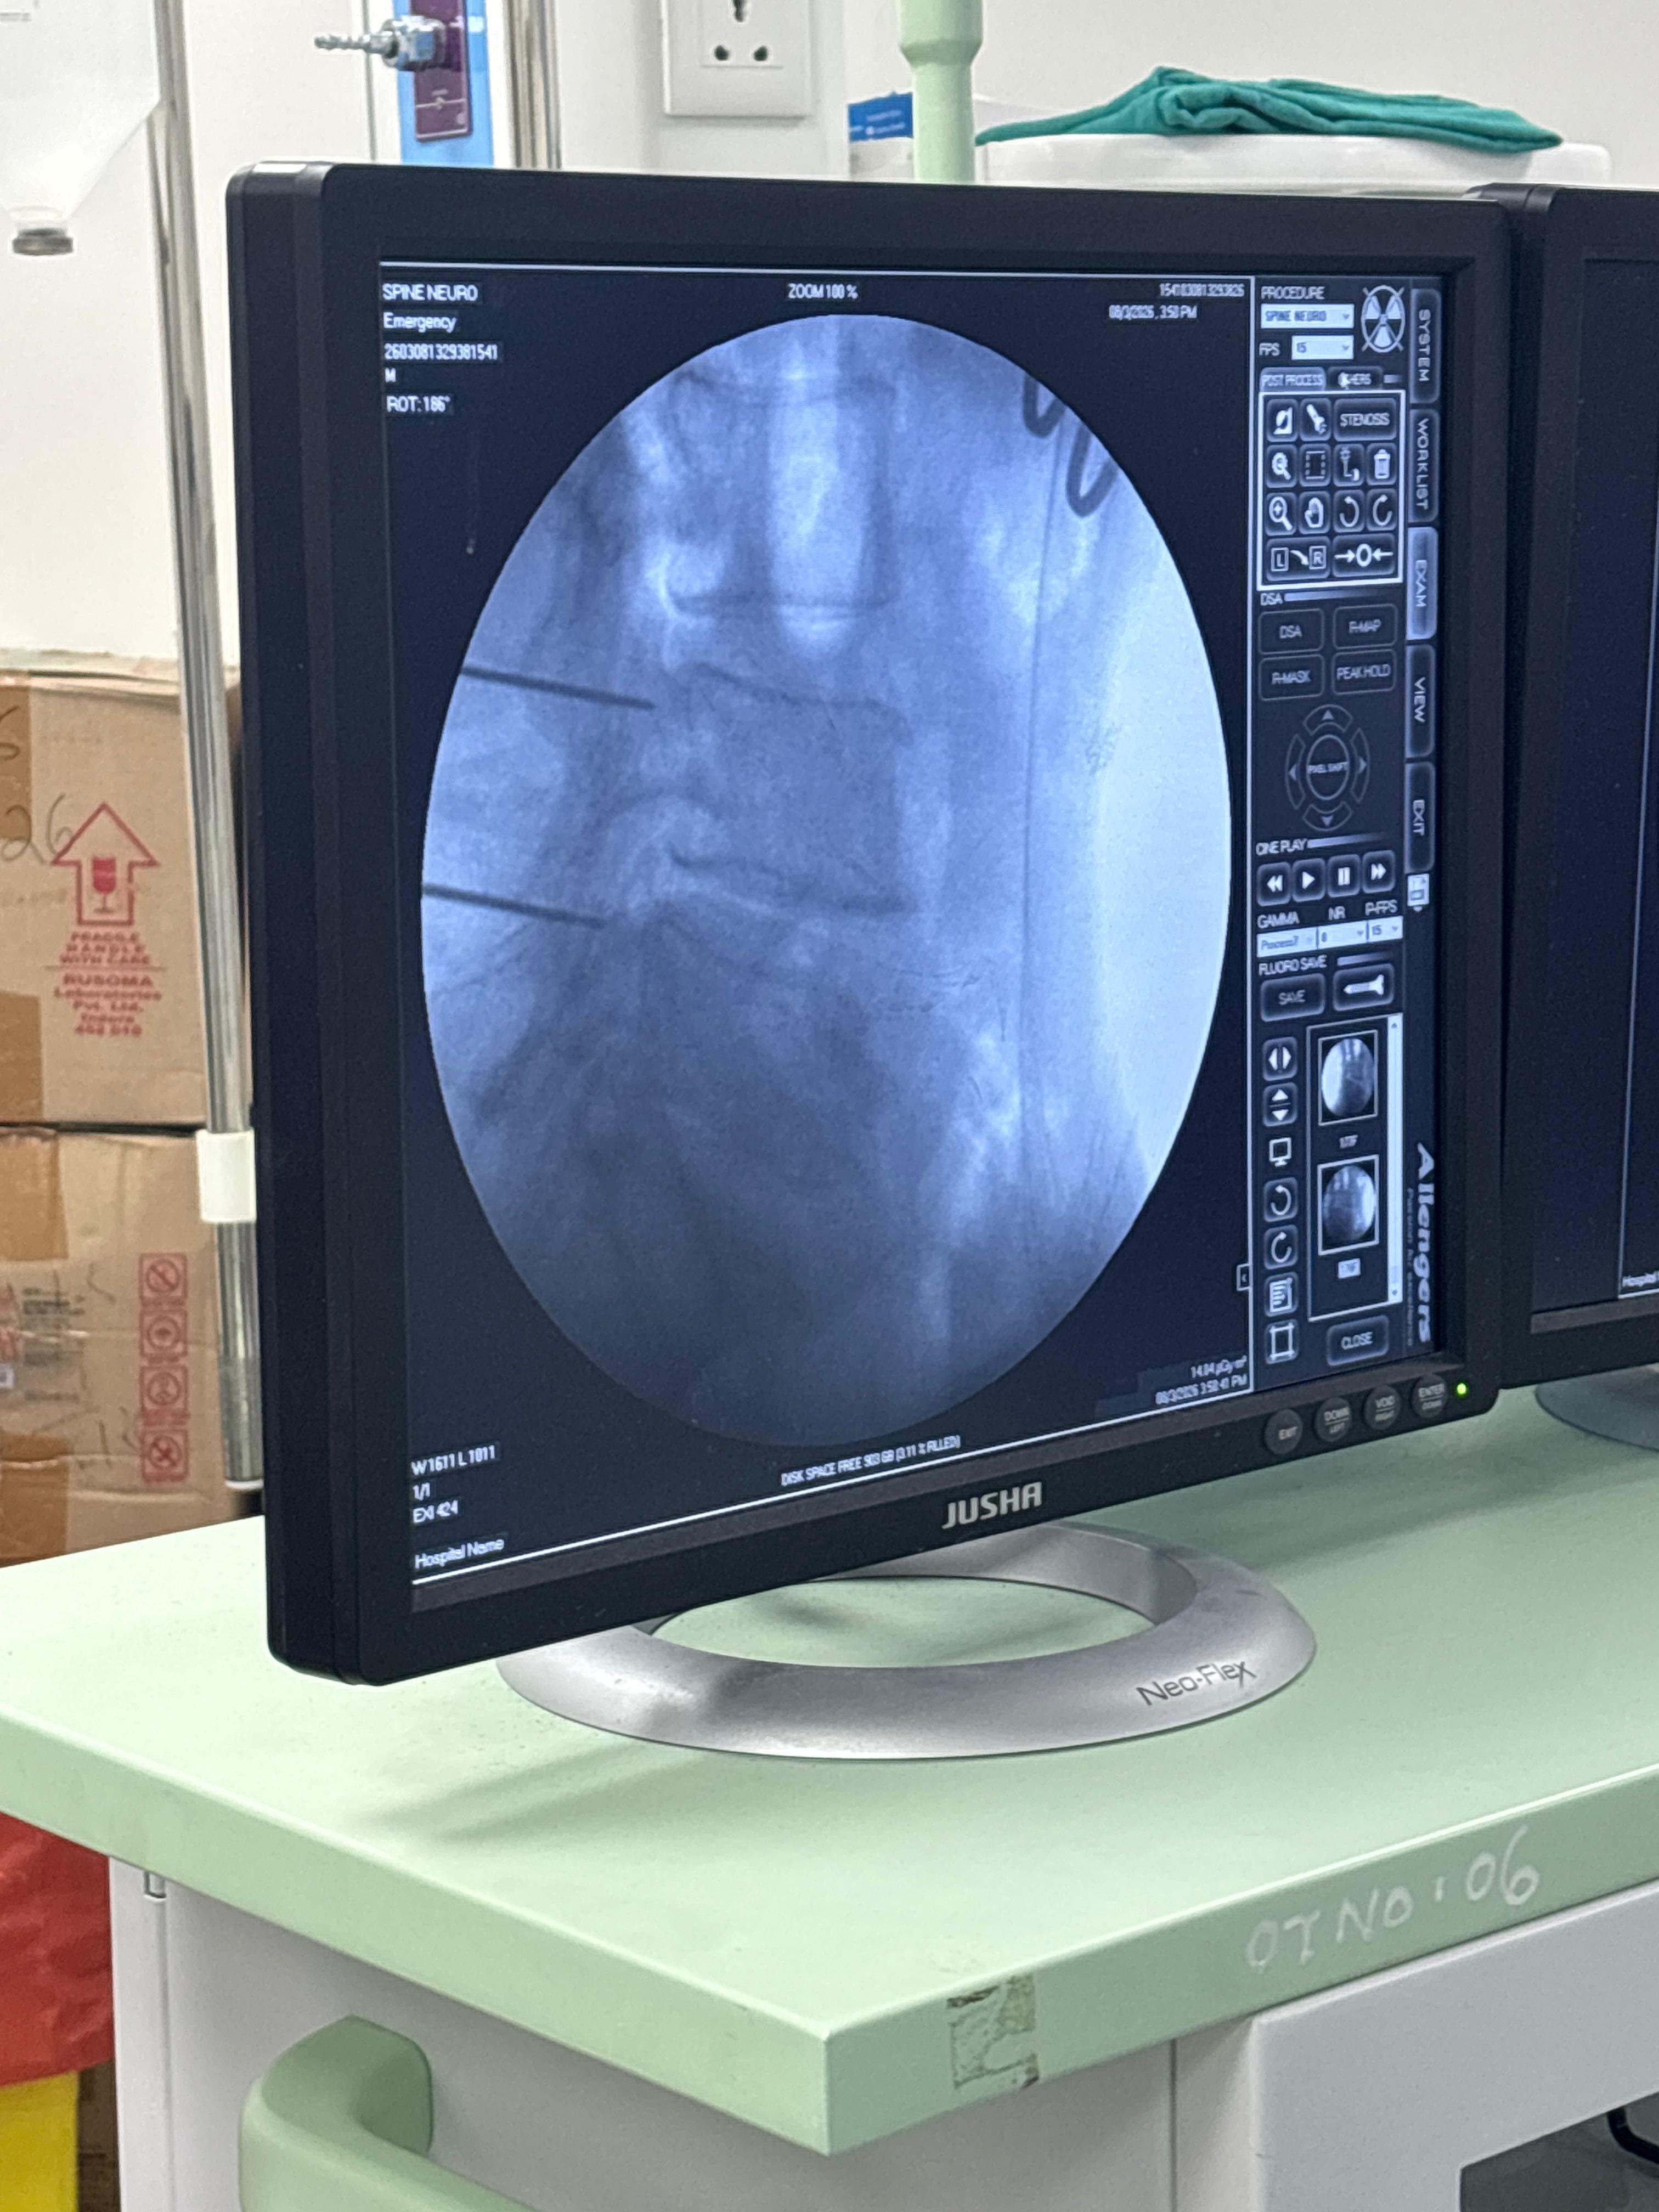

Successfully conducted a CME on the role of Radiofrequency Ablation in various Chronic Pain Management by the Department of Anaesthesia, GMC Surat with ISSP branch Surat. Moved one step ahead for advanced pain management with live workshop.. Successfully conducted live cases with Pain physicians from Surat and national faculties. Guest: Dr J Brahmbhatt, Dean GMC surat, Dr Hari Menon, Professor Orthopaedic dept and GMC Observer, Dr Kothari Renowned Pain Physician from Mumbai, Dr Namrata Bhagvat and other state and local faculties with 60 participants. Morning session was conducted with lectures & discussion with recorded cases from various faculties. And afternoon session was various Chronic pain management by intervention by radio frequency ablation and live displayed those cases from OT side to auditorium.